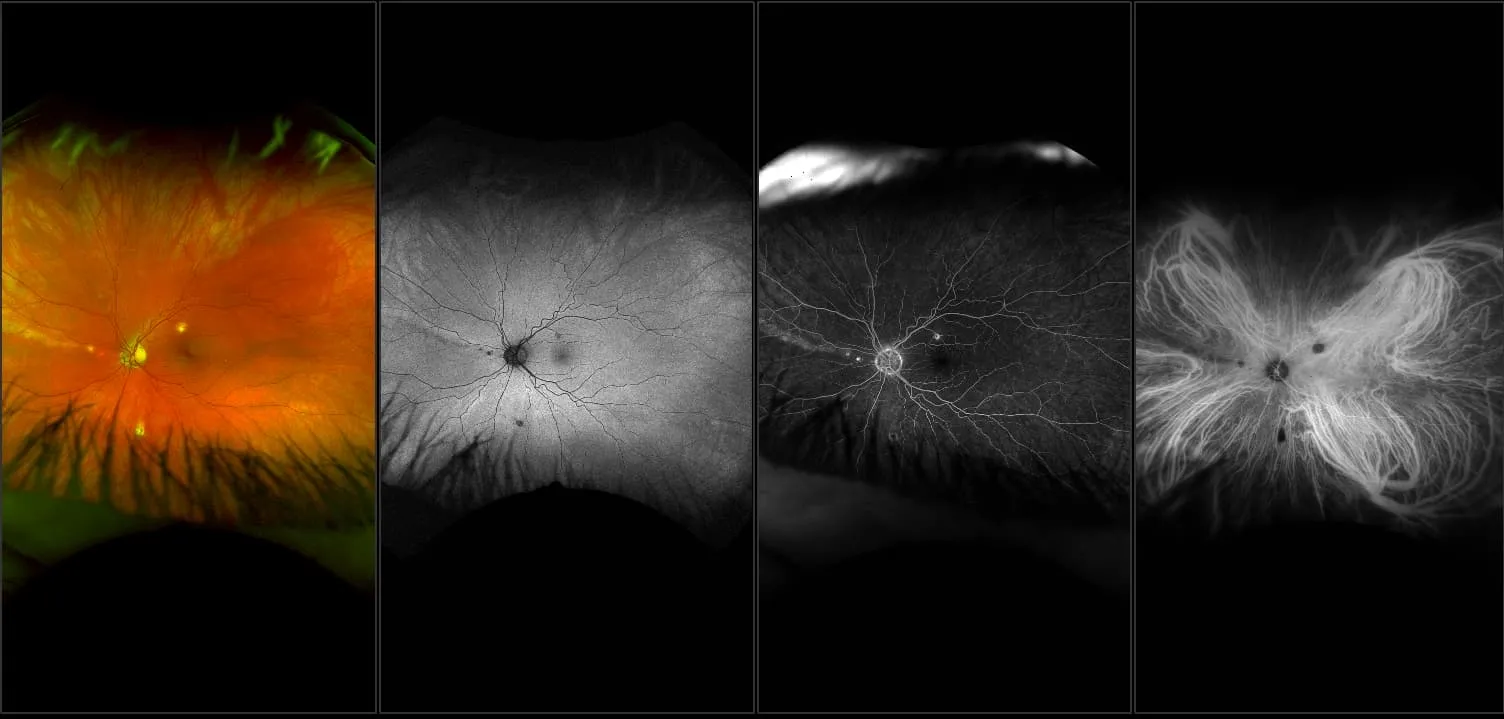

optomap® Recognizing Pathology

This material is designed as a searchable reference resource to support clinical decision-making. The information contained here should be used as general guidance when viewing optomap and OCT images from Optos devices. The differential diagnosis should be made under the direction of the responsible physician. These images were taken on the latest ultra-widefield optomap devices.

The Cases and Images

optomap Recognizing Pathology is searchable by pathology and/or optomap image modality. You may search by multiples of each selection. Each individual case is represented by the accompanying thumbnail image. Most cases include several different optomap image modalities. To view a full description of the case, please click on the thumbnail. Each image in the case will be made available through our OptosAdvance software which provides multi-dimensional visualization of digital images to aid in the analysis of anatomy and pathology. Support and pathology definitions can be found by selecting one of the buttons, above. Should you have questions, please complete the form below.